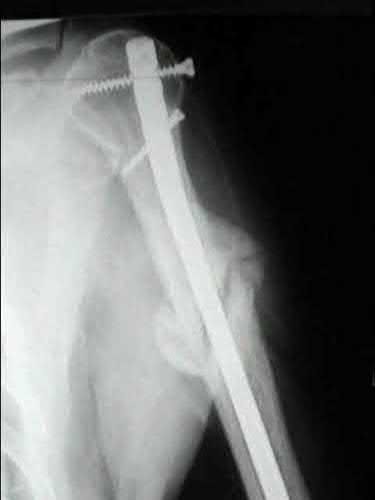

A 35-year-old-male sustains the fracture seen in Figure A. Which of the following reduction forces must be applied to the proximal fragment to correct the deformity commonly seen in these fractures?

Figure A demonstrates a displaced subtrochanteric femur fracture with an intact lesser trochanter. The pull of iliopsoas on the lesser trochanter as well as the intact external rotators and gluteal musculature results in the the proximal fragment being in a flexed and externally rotated or abducted position (the most common post operative deformity). Reduction manuevers must be biologically friendly but also counteract the flexion/abduction moment. Lundy's review article discusses evaluation and treatment of subtrochanteric fractures. The review article details the various implants often used which include 95 degrees plates, femoral reconstruction nails, or trochanteric femoral nails with interlocking options. Lundy's article discourages the use of the 135 degree screw and side plate combo due to high failure rates in these fracture patterns. Bedi et al also review treatment of these fractures and discuss common

problems of malunion, nonunion, and implant failure. The article reviews reduction techniques that are soft tissue friendly, as well as the use of appropriate implants in these fracture types.